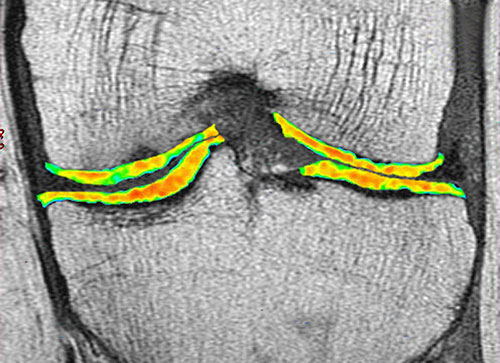

Improved cartilage mapping and injury grading techniques are used by radiologist at NHS Hospital Jalandhar to evaluate and measure the damage even the quality of cartilage and its function by using advanced techniques like Cartigram MRI.

This helps the physicians and surgeons to create individualised patient care to realise better clinical outcomes.